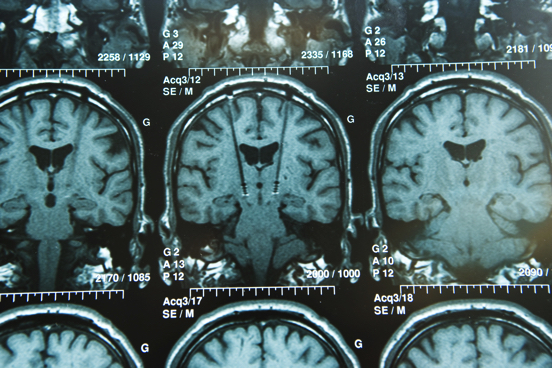

Estimulació cerebral profunda o estimulació pal·lidal

Consisteix a col·locar dos elèctrodes als nuclis pàl·lids del cervell mitjançant una tècnica d’estereotàxia, per millorar la funcionalitat motora i la qualitat de vida. Els pacients candidats a estimulació pal·lidal són els que presenten distonies primàries que no tenen lesió estructural en el sistema nerviós central.